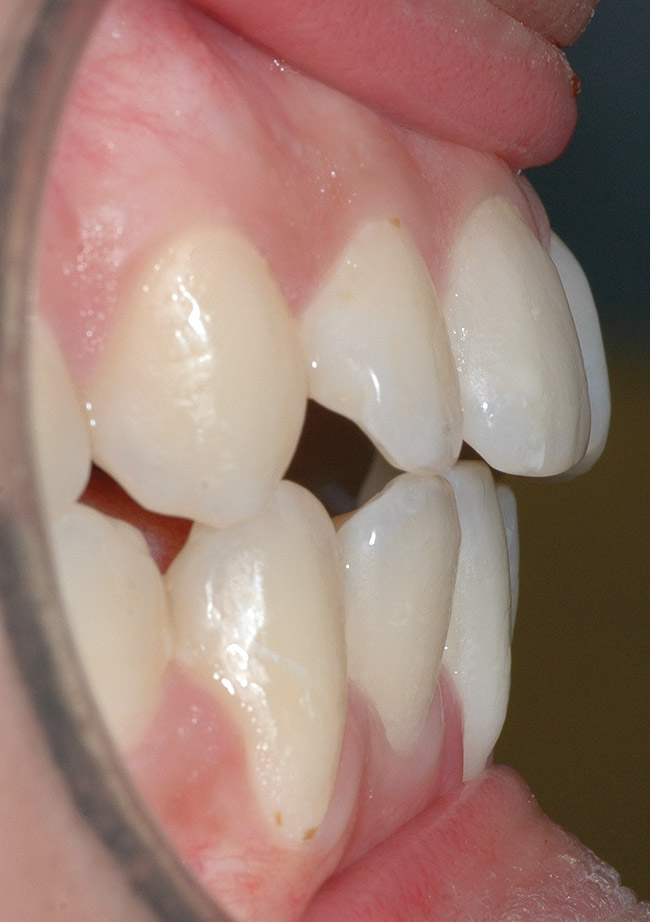

CASE 3 Fig 6. Post-orthodontic Miller Class II recession recommended for orthodontic treatment. Clinical view 5 years after orthodontic treatment showing a buccally displaced root of the lower incisor.

Figure 6